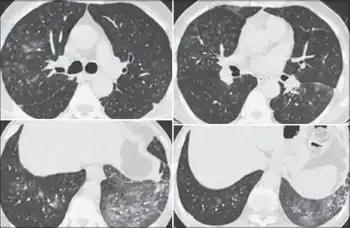

It can be difficult to accurately diagnose a patient with byssinosis due to symptoms that are similar to other respiratory diseases such as chronic obstructive pulmonary diseases (COPD), asthma, or bronchitis.[4] Byssinosis can be misdiagnosed as other pneumoconioses therefore a chest x-ray and/or lung function test is needed to accurately diagnose a patient who may have byssinosis.[4] The main distinction of byssinosis from other respiratory diseases comes from the initial exposure. Patients who have byssinosis have typically been exposed to cotton or just dust for an extended period of time and experience symptoms of chest tightness and coughing.[3]

Patient history should reveal exposure to cotton, flax, hemp, or jute dust. Measurable change in lung function before and after working shifts is key to diagnosis. Patients with byssinosis show a significant drop in FEV1 over the course of work shift. Chest radiographs show areas of opacity due to fibrosis of the pulmonary parenchyma.